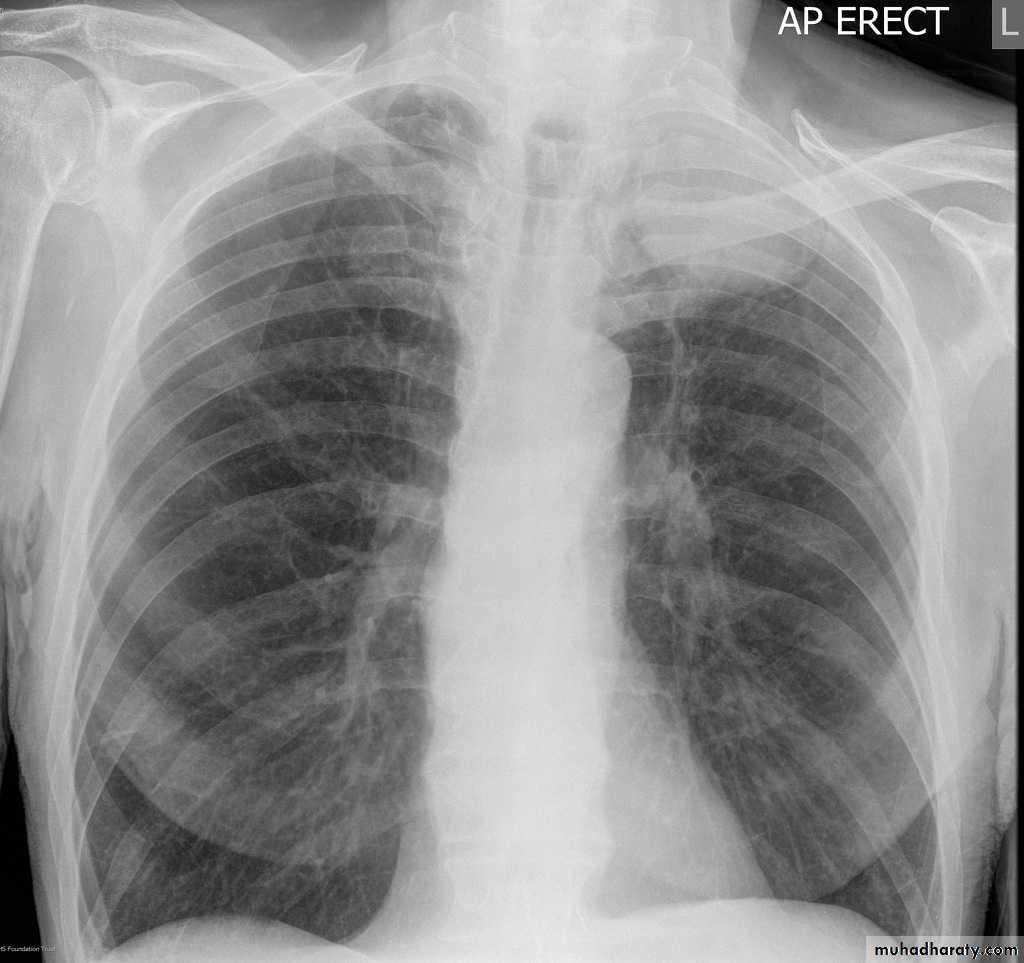

Post primary TB radiographic appearance

Post-primary pulmonary tuberculosis, also known as reactivation tuberculosis or secondary tuberculosis occurs years later, frequently in the setting of a decreased immune status. In the majority of cases, post-primary TB within the lungs develops in either :

* posterior segments of the upper lobes

*superior segments of the lower lobes

Typical appearance of post-primary TB

1.patchy consolidation or poorly defined linear and nodular opacities in both apices , upper zone in one lung , & lower zone in other lung ( ulternating lesion ) .2. Post-primary infections are far more likely to cavitate with multiple abscess formation & air fluid level more develop in the posterior segments of the upper lobes.

3. Tuberculomas seen in post-primary TB and appear as a well defined rounded mass typically located in the upper lobes .